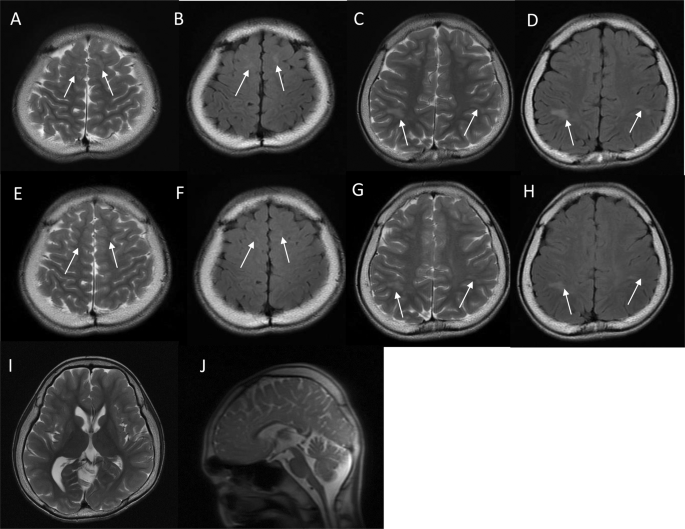

The index patient was an 18-year-old male who had been born to nonconsanguineous parents at 40 weeks and 6 days. The family history included no reports of intellectual disability, developmental delay, or epilepsy. At birth, his weight was 2604 g (−2.2 SD), his body length was 44.5 cm (−2.9 SD), and his head circumference was 30.5 cm (−2.4 SD); there was no birth asphyxia. He underwent palate surgery with a Hotz-type plate at 6 days, 1 month, 2 months, 6 months, and 10 months to repair a cleft palate and lip. At age 11, he underwent cleft palate bone graft surgery. He was able to control his head at the age of 3 months, independently sat at the age of 12 months, and independently walked at the age of 2 years and 3 months. By age 18, he had never uttered any meaningful words. His Tsumori–Inage infant mental development quotient was 20 at the age of 7 years and 12 at the age of 17 years. He was diagnosed with autistic spectrum disorder due to obsessive-compulsive behavior and impairments in social interaction and social communication. He experienced his first febrile seizure at the age of 1 year. At the age of 1 year and 6 months, he had five episodes of febrile seizure, and valproate was initiated. The febrile seizure episodes gradually decreased, disappearing entirely at the age of 3 years and 6 months. At the age of 7 years and 1 month, he discontinued valproate at his parents’ discretion. At 7 years and 2 months, he experienced his first nonfebrile general atonic seizure with cyanosis. After he resumed valproate, his seizure episodes ceased. At 12 years and 2 months, his valproate dose was gradually tapered off, but generalized clonic seizures occurred at the age of 12 years and 8 months. The patient resumed valproate, and his seizure episodes ceased. After 4 years without seizure episodes, valproate was gradually tapered off by age 17. Generalized seizures recurred three months later; accordingly, the same 400 mg dose of valproate was resumed. The patient had undergone interictal electroencephalography (EEG) multiple times since early childhood, but there were no abnormal findings. His first head MRI, taken at the age of 11 years, showed multiple T2/FLAIR high-intensity lesions in white matter and slightly enlarged ventricles (Fig. 1A–D and I). MRI showed no morphological abnormalities in the corpus callosum or brainstem (Fig. 1J). At 14 years of age, physical descriptions of large ears, deep-set eyes, and a wide-based gait were recorded, but no photographs were taken (the parents did not consent to facial photographs). At 16 years of age, his body weight was 41.5 kg (−2.0 SD), his body height was 162.7 cm (−1.3 SD), and his head circumference was 51.8 cm (−3.2 SD). The T2/FLAIR high-intensity lesion on MRI gradually decreased (Fig. 1E–H).

Neuroimaging of the patient at A–D and I, J 11 years of age and E–H 15 years of age. A, C, E, G, I and J T2-weighted magnetic resonance imaging. B, D, F, and H Axial fluid-attenuated inversion recovery (FLAIR) magnetic resonance imaging. A–D Axial T2/FLAIR images showing hyperintense signals in white matter within the frontal and parietal lobes (arrows). The U-fibers were spared. I Axial T2-weighted imaging showed a slight enlargement of the left ventricle. J Sagittal T2-weighted imaging showed no morphological abnormalities in the corpus callosum or brainstem. E–H As in the image taken at 11 years of age, T2/FLAIR imaging showed hyperintense signals in white matter within the frontal and parietal lobes (arrows). The signal intensity of each lesion was lower in this image than in the one taken at 11 years of age.

Ventricular enlargement has already been reported in a patient with DYRK1A-related intellectual disability syndrome [1, 9]. In follow-up MRIs of the present patient, the white matter lesions had slightly reduced signal intensity compared to the first image. Ji J et al. described similar white matter lesions as gliosis [1]. DYRK1A has been noted to play an important role in neurogenesis, and white matter lesions in patients with pathogenic variants of DYRK1A may arise during the early development of the brain. However, such white matter lesions can also be caused by other factors that are not known to be associated with this gene, such as inflammation, vascular abnormality, and infection. The pathogenesis of white matter lesions in patients with pathogenic DYRK1A variants is unknown. The correlation between genotype and white matter abnormality is unknown in this disorder, and case with a different variant causing the same amino acid change did not show white matter abnormality [5].